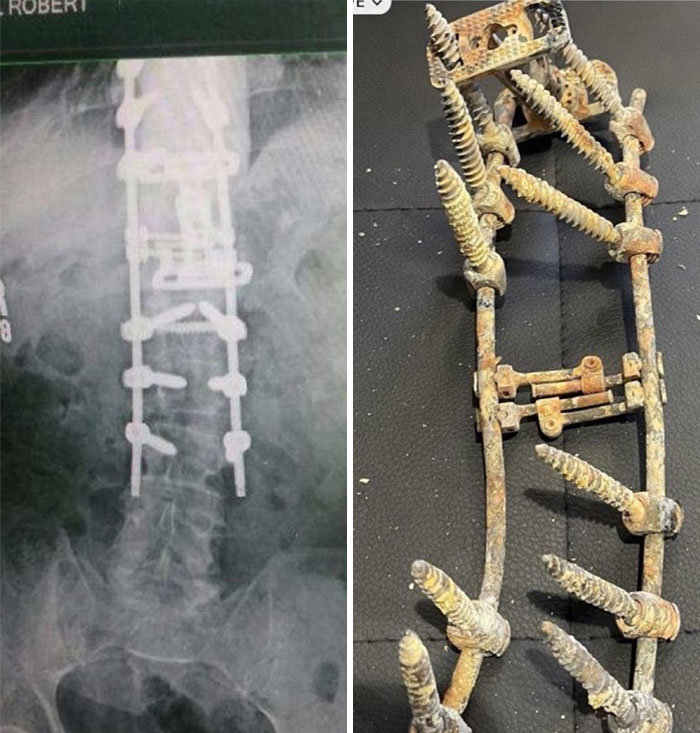

An X-ray showing Robbie Knievel’s spine and an actual photograph of the metal device after he passed away in January 2023.